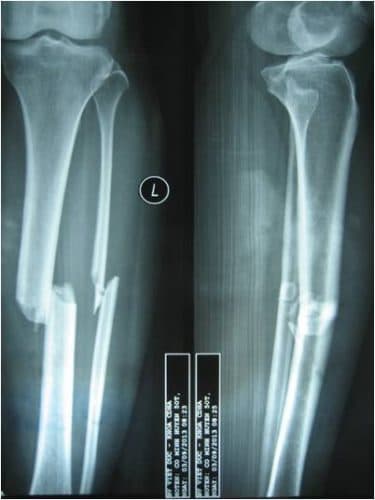

- Triệu chứng trên X-quang: Cần chụp X – quang hai tư thế thẳng và nghiêng, chụp toàn bộ cẳng chân lấy cả khớp gối và khớp cổ chân. Hình ảnh trên X-quang cho thấy rõ vị trí của xương chầy và xương mác, hình thái đường gãy và mức độ di lệch.

Hình ảnh trên X-quang cho thấy rõ vị trí của xương chầy và xương mác, hình thái đường gãy và mức độ di lệch.